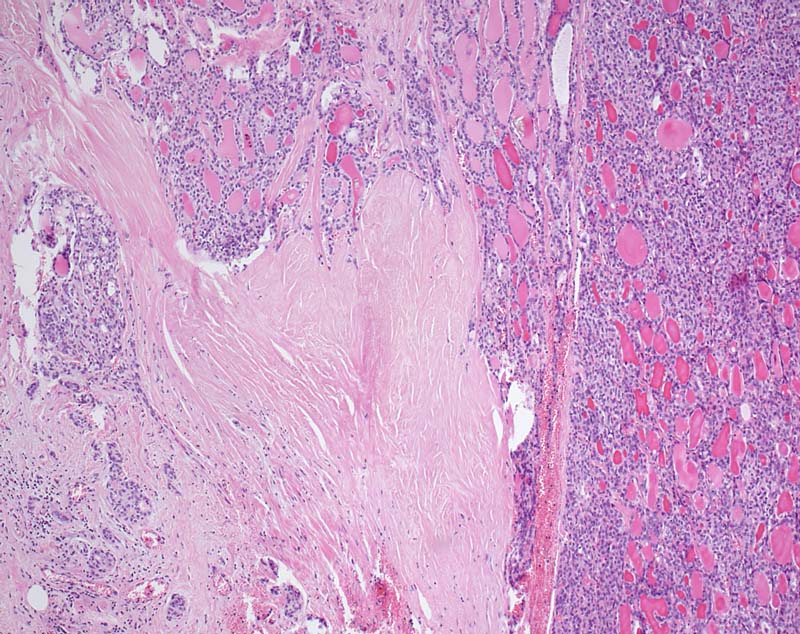

Der follikuläre Tumor durchbricht die breite bindegewebige Kapsel.

Kapseldurchbrüche mit ausgedehnter Invasion des benachbarten Gewebes fanden sich an zahlreichen Stellen. Somit handelt es sich um ein grob invasives follikuläres Karzinom.